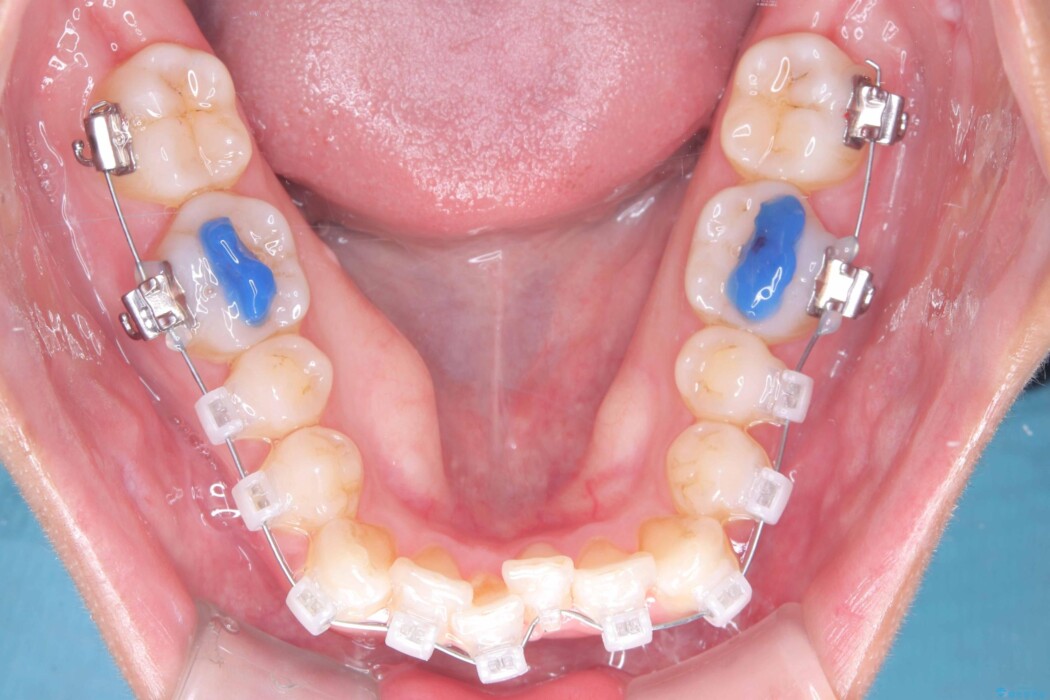

矯正検査の結果、非抜歯にてワイヤー矯正を行うこととしました。

ガタつきのほかに反対咬合も認められたため、見た目だけでなく嚙み合わせも同時に改善していきます。

歯の移動量や力のコントロールを最適化することで、短期間で治療完了しました。